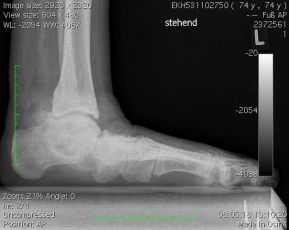

Ein erworbener Plattfuß – medizinisch als Pes planovalgus bezeichnet – ist mehr als nur eine Fußformabweichung. Besonders im Erwachsenenalter kann er zu dauerhaften Schmerzen führen, wenn das Fußgewölbe absinkt, die Ferse nach außen kippt und das Gleichgewicht des gesamten Bewegungsapparates gestört wird. Die gute Nachricht ist: In vielen Fällen helfen konservative Maßnahmen, wie Einlagen, fußgymnastische Übungen, Physiotherapie oder orthopädische Schuhe. Wenn diese Maßnahmen nicht mehr greifen, ist abzuwägen ob und wann eine operative Maßnahme erforderlich ist.

Der Plattfuß im Erwachsenenalter kann angeboren sein, sich verschlimmert oder sich über Jahre entwickelt haben. Ursächlich ist oft eine Schwächung oder Überlastung des Bandhalteapparats und/oder der Tibialis-posterior-Sehne*, die für die Aufrechterhaltung des Fußlängsgewölbes zuständig sind. Reißen diese Strukturen oder sind sie beschädigt, kann das Fußgewölbe funktionell und strukturell gestört sein und entsprechende Folgen nach sich ziehen.

Typisch Merkmale für einen erworbenen adulten Plattfuß sind:

- ein abgeflachtes oder vollständig eingesunkenes Fußlängsgewölbe,

- eine nach außen gekippte Ferse, eine sogenannte Valgusstellung,

- eine nach außen gedrehte Vorfußposition, eine sogenannte Abduktion,

- zunehmende Instabilität beim Gehen oder Stehen,

- Schmerzen entlang der Fußinnenseite, vor allem beim Abrollen,

- im Spätstadium auch Schmerzen am Aussenknöchel.